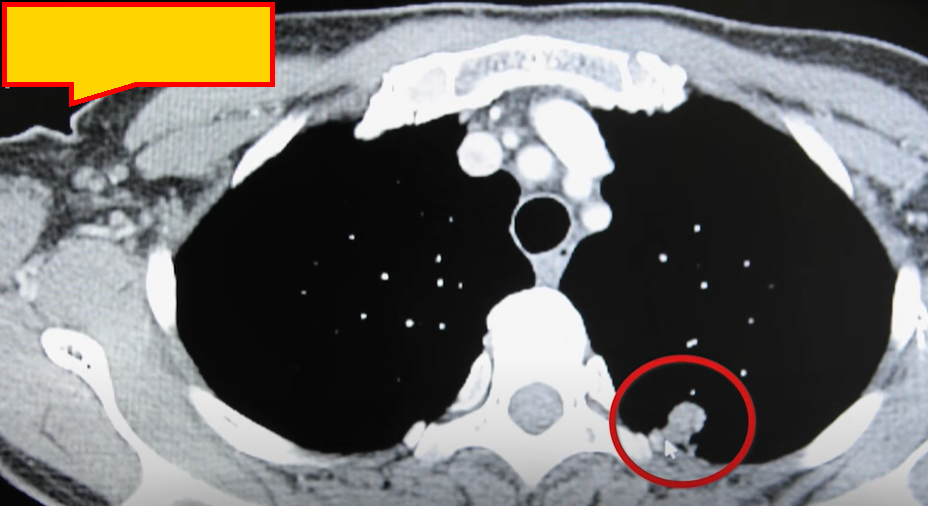

영상 검사: CT(전산화단층촬영), MRI(자기공명영상), 초음파 등이 사용됩니다. 각 검사의 장점을 바탕으로 종양의 특성을 확인합니다.

경과 및 합병증

침샘암 치료 후에는 다양한 합병증이 생길 수 있으므로 이에 대한 대응이 중요합니다.